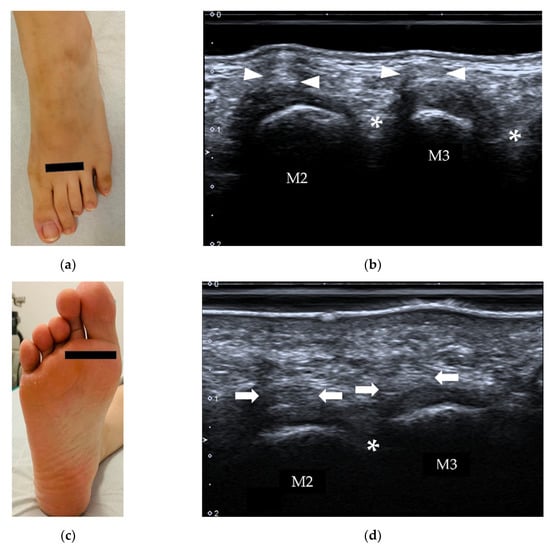

4.3. Morton’s Neuroma

| Morton’s neuroma | intermetatarsal spaces between the 3rd and 4th metatarsal heads | fusiform, hypoechoic mass with “rat’s tail sign” |